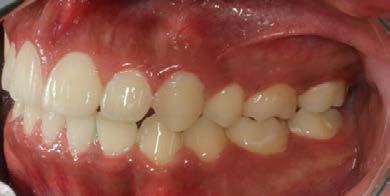

Se presenta una paciente clase ll esquelética en los estudios extrao rales en la fotografía de frente se ve hiperdivergente con una mordi da profunda de 5mm, un diastema, y refiere como motivo de consulta "no me gusta el espacio entre mis dien tes" (Figura 1).

En los estudios intraorales de inicio en las fotografías se muestra en la de frente el diastema anterior, con la línea media dental superior e inferior no coincidentes, la mordida profun da anterior (Figura 2), en la lateral derecha clase l molar y canina bila teral (Figura 3), el apiñamiento leve superior e inferior y la forma de las arcadas.

Estudios intraorales finales

En las fotografías intraorales finales se ve la corrección del apiñamiento maxilar y mandibular, la forma de las arcadas es ovalada, se consiguió guía de desoclusión canina derecha e izquierda, la mordida profunda

anterior (Figura 10), la estabilidad oclusal, la máxima intercuspidación, el paralelismo radicular y oclusión funcional, el cierre de diastema ante rior, las líneas medias superior-infe rior coincidieron ambas con la facial.